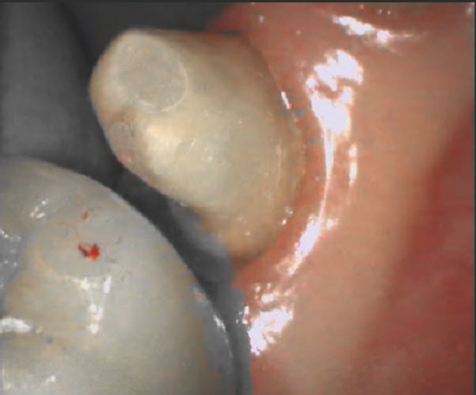

구강 스캔 전 환자의 구강 상태를 확인해야 합니다. 구강 내에 혈액/타액이 과도하게 있는 경우 스캔 데이터에 영향을 줄 수 있으므로 스캔 전 반드시 혈액과 타액을 제거해야 합니다.

구강 스캐너는 구강 상태를 있는 그대로 획득하여 데이터를 생성하기 때문에, 치은 연하 마진 또는 불분명한 마진 케이스의 경우 정확한 마진 데이터 획득을 위해 치은 격리가 필요합니다.

치은 격리 방법은 레이저를 이용한 치은 절개, 치은 압배사를 사용한 격리 등이 있습니다.

| 올바르지 않은 구강 환경 | 올바른 구강 환경 |